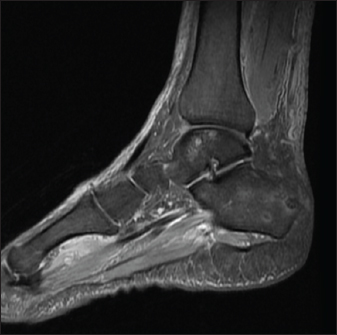

A 70-year-old male known to have diabetes mellitus presented with a 1 month history of fever and weight loss. History of multiple hospital visits and several courses of oral and intravenous antibiotics were present. Physical examination revealed hepatosplenomegaly. As he was fitting the criteria for Pyrexia of Unknown origin, work for the same was done. Routine investigations showed neutrophilic leucocytosis with raised inflammatory markers. Widal was negative. Ultrasound abdomen showed features of chronic liver disease. Contrast CT scan of abdomen showed splenic infarcts. He was started on antibiotics, but he had ongoing fever spikes. While in hospital he developed difficulty in walking due to left ankle pain. MRI foot (Fig. 1) was taken showed small intraosseous abscess in calcaneal bone. Blood cultures grew B. pseudomallei. The patient had a good recovery and was followed up in the outpatient clinic ray foot (Fig. 2) was repeated showed a resolution of osteomyelitis.

Fig. 1. MRI Rt foot—patient 1.